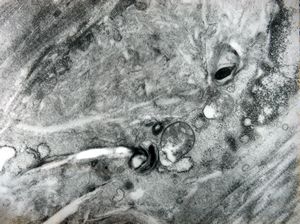

F,31y. | demyelinating hypertrophic neuropathy - n. suralis- bands of Büngner with collagen-filled pockets